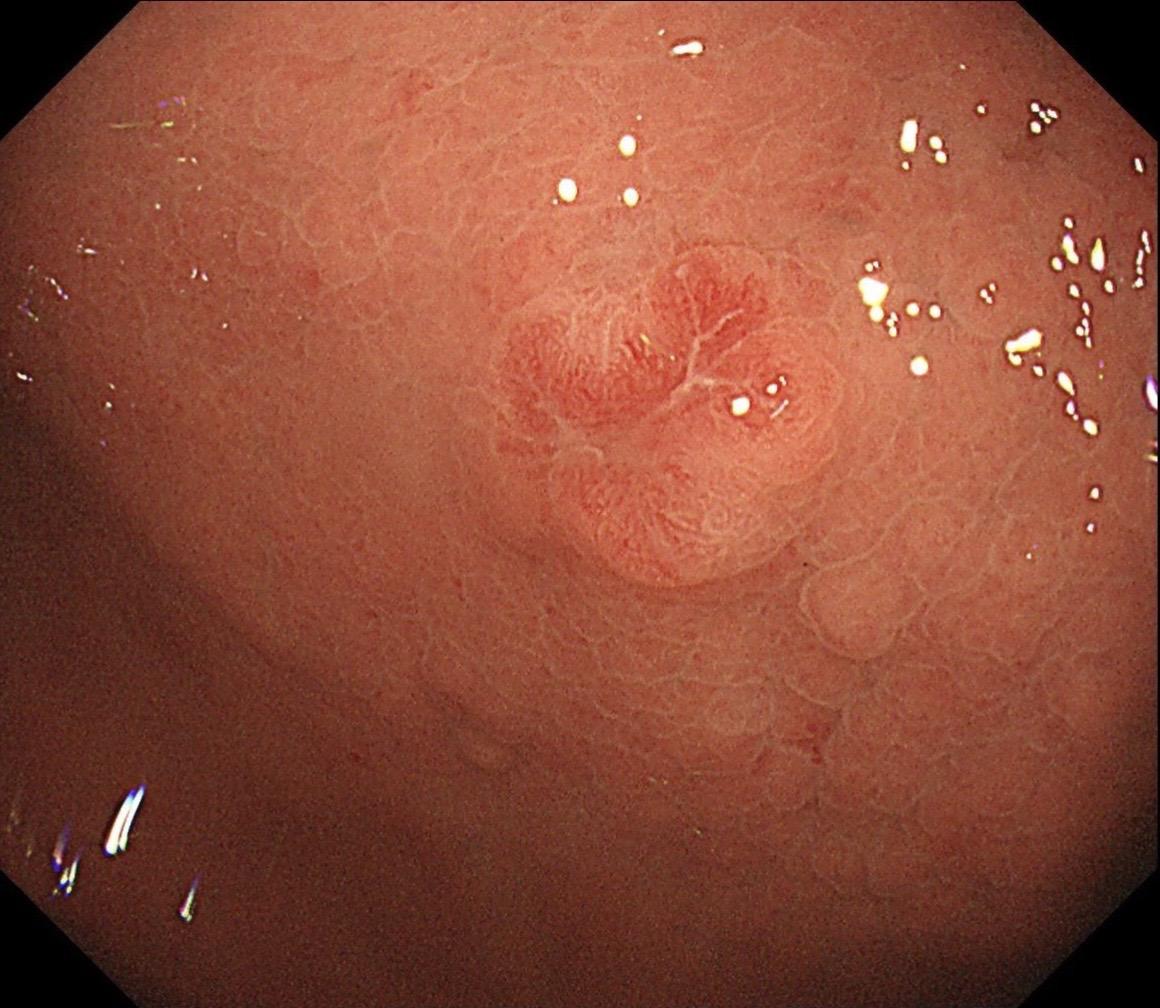

男,70岁,胃底体双发病变。看图猜猜病理呢……尤其胃底这个小的~凹陷性病变,当中央结构观察欠清时,边缘的异常微血管往往有提示作用,哪怕是局部。两处都考虑早期病变,拟ESD微创治疗。